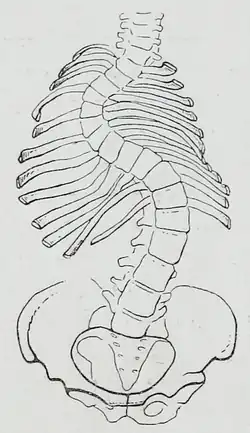

Congenital scoliosis can be attributed to a malformation of the spine during weeks three to six in utero due to a failure of formation, a failure of segmentation, or a combination of stimuli.[47] Incomplete and abnormal segmentation results in an abnormally shaped vertebra, at times fused to a normal vertebra or unilaterally fused vertebrae, leading to the abnormal lateral curvature of the spine.[48]

Vertebrae of the spine, especially in the thoracic region, are, on average, asymmetric.[12] The mid-axis of these vertebral bodies tends to point systematically to the right of the median body plane. A strong asymmetry of the vertebrae and their musculature, may lead to mechanical instability of the column, especially during phases of rapid growth. The asymmetry is thought to be caused by an embryological twist of the body.[50]